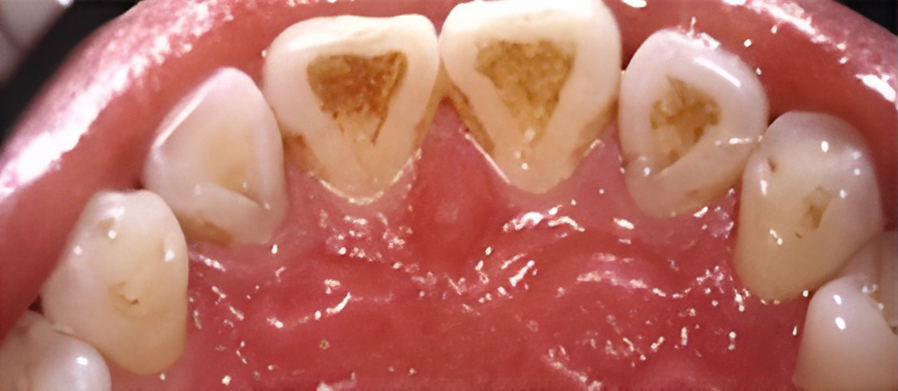

칫솔질과 치실질을 통해 매일 플라그를 제거하지 않으면 박테리아로 인해 잇몸 조직이 붉어지고 부어오르게 됩니다. 염증이 더 심해지면, 치아 주위 조직에 염증이 생기는 치주염으로 진행될 수 있습니다.

보통 치은염은 칫솔질을 꼼꼼하게 열심히 하고 치실을 사용함으로써 건강한 잇몸을 회복할 수 있습니다. 올바른 칫솔질과 정기적인 스케일링으로 세균이 자랄 수 있는 환경을 제거하면 잇몸을 건강하게 유지할 수 있습니다.

치은염을 치료하지 않고 방치하면 플라그가 뿌리로 퍼져 뼈와 연조직에 감염과 손상을 일으킬 수 있습니다. 잇몸이 치아에서 분리되어 물러나기 시작할 수 있으며 잇몸 라인 아래에 주머니가 생겨 플라크와 음식물이 쌓일 수 있습니다.